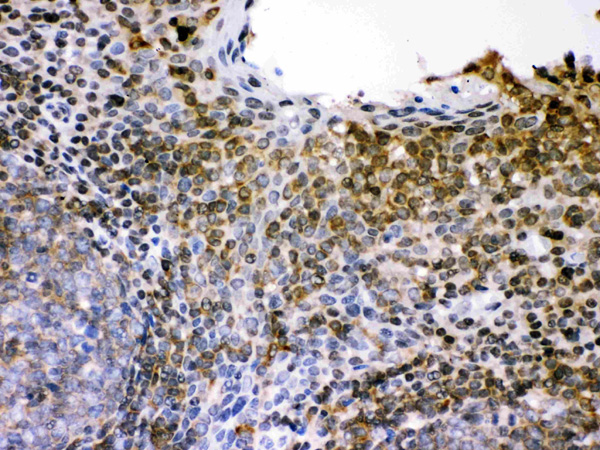

IHC (Immunohistochemistry)

(Anti- L-selectin Picoband antibody, AAA46271, IHC(P)IHC(P): Human Tonsil Tissue)